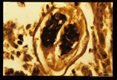

Low power view of an inflammatory pulmonary nodule around a Brugia.

Brugia